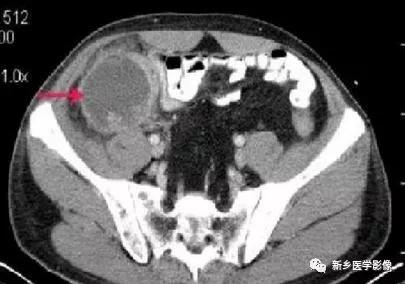

(2)CT:右下腹/盆腔囊性肿块,壁薄或厚,增强环形强化,内部可见粪石;也可为边界不清、密度不均软组织影,强化不明显。肿块与盲肠关系密切,与周围结构粘连,内可见小气泡/气液平面。临近肠曲反射性淤积,可伴气液平面。

(3)CT:盲肠尖区域薄壁囊性肿块,边界清晰,呈长圆形,与盲肠间解剖关系密切,环形钙化壁。增强壁强化,内容物无强化。腔内出现气泡/气液平伴感染。腹膜假黏液瘤典型为腹膜分叶病变,使空腔脏器移位或变形,实质器官边缘呈“扇贝”改变。